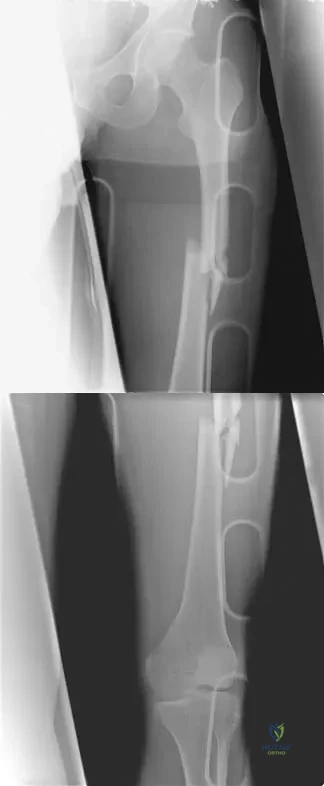

A 51-year-old man sustained an open fracture of his tibia in Korea 42 years ago. An infection developed and it was resolved with surgical treatment. For the past 6 months, an ulcer with mild drainage has developed over the medial tibia. The ulcer is small and there is minimal erythema at the ulcer site. A radiograph and MRI scan are shown in Figures 43a and Figure 43b. Initial cultures show Staphylococcus aureus susceptible to the most appropriate antibiotics. Laboratory studies show an erythrocyte sedimentation rate of 70 mm/h. What is the most appropriate surgical treatment at this time?

A 40-year-old man has a palpable mass over the dorsum of the ankle. He reports no history of direct trauma but notes that he sustained a laceration to the middle of his leg 6 weeks ago. Examination reveals a 4-cm x 1-cm mass. T1- and T2-weighted MRI scans are shown in Figures 12a and 12b. An intraoperative photograph and biopsy specimen are shown in Figures 12c and 12d. What is the most likely diagnosis?